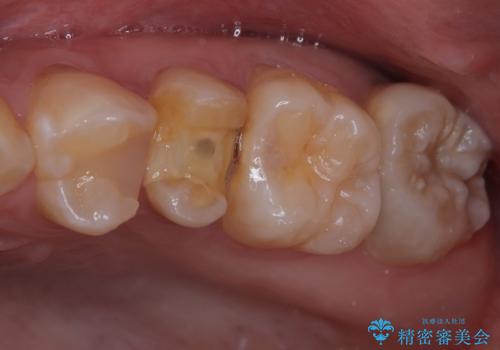

- 左上の前から5番目の金属の詰め物(メタルインレー)が取れたとのことで来院された患者様です。一時帰国中とのことで短期間での治療を希望されていました。土台はファイバーコアがしっかり入っていたため、そのまま利用することにしました。根管治療は症状もなく、レントゲン上でも病変を認めないため患者様と相談して根管治療を行わないことにしました。拡大鏡の視野下において、虫歯を除去して元々の詰め物の範囲も大きいためオールセラミッククラウンに適した形に整えました。